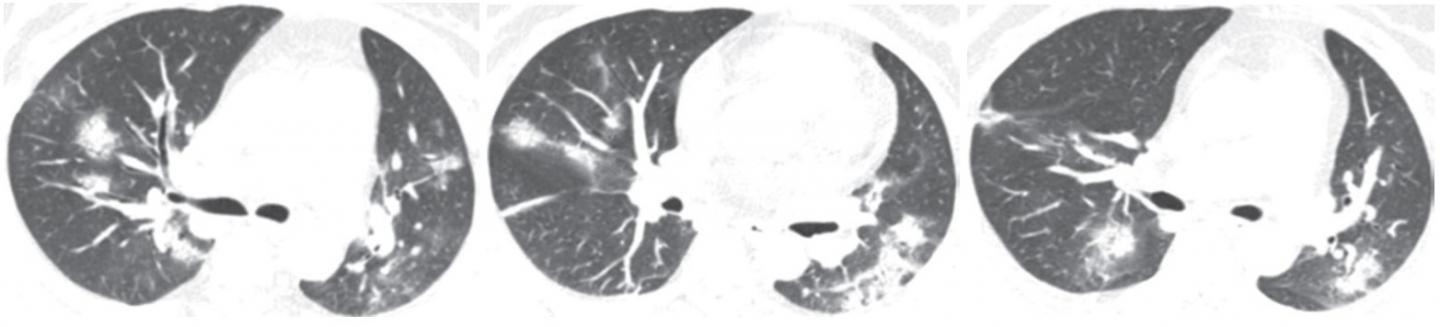

As Li and Xia explained: "CT of one of the two patients with confirmed adenovirus infection showed ill-defined patchy ground-glass opacities (GGOs), segmental and subpleural consolidations in both lungs, and pleural effusion. CT of the other patient showed subpleural GGOs and consolidation with vascular enlargement, interlobular septal thickening, and air bronchogram sign."

The CT findings seen in Li and Xia's two adenovirus cases were similar to those observed in their COVID-19 cases.

The two authors also found CT features of COVID-19 that differ from both severe acute respiratory syndrome coronavirus (SARS-CoV) and Middle East respiratory syndrome coronavirus (MERS-CoV): a reversed halo sign in two patients (3.9%) and pulmonary nodules with a halo sign in nine patients (17.6%).